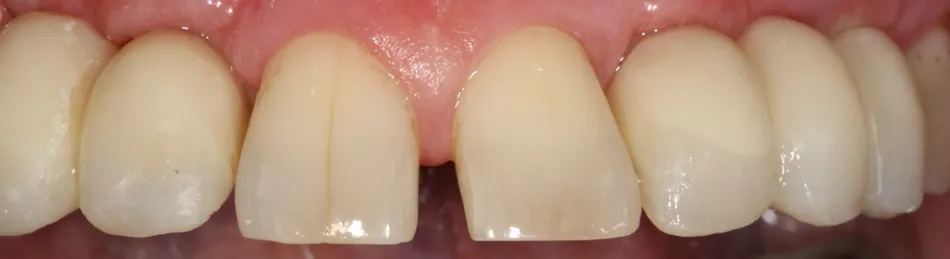

12. State of the soft tissues 8 months after insertion of the implants and 6 months after wearing bridges. Soft tissue volume was satisfactory. A crown was fitted to tooth 15.

16a-b. Final situation after inserting bridges to 15 Ncm, cementing the crown to tooth 15, and gluing the veneers to teeth 11 and 21.

16c. 4 years post implant placement.